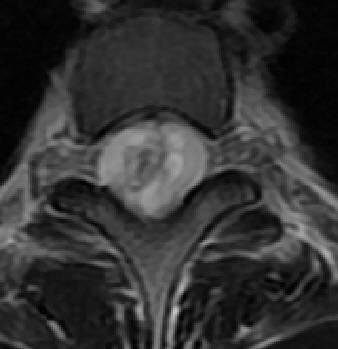

MRI

可提供腰椎管的矢状面、冠状面和轴位横断面上的影像。椎管狭窄以T2加权像显示较好,脑脊液为高信号,产生所谓“脊髓造影”的效果,而骨质增生,骨赘、间盘均为低信号,能清晰地显示椎管狭窄,以及对脊髓的压迫情况。但对肥大的黄韧带、骨质增生等的判断则不如较高清晰度CT扫描。

腰椎正常MRI解剖。

腰椎管狭窄MRI表现。